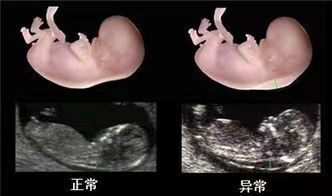

正常胎儿淋巴系统建立之前,少量淋巴液聚集在颈部淋巴管内形成积液,即NT。所有胎儿都存在颈项积液,反映在超声图像上,即为胎儿颈椎水平矢状切面上测量颈后皮肤至皮下组织之间无回声层的最大厚度,其数值随孕周增大而增厚,但一般不超过3.0mm。当胎儿出现淋巴回流障碍时,过多的淋巴液聚集就会出现NT增厚,当淋巴管扩张就会出现颈部水肿或颈部水囊瘤。

一般NT增厚以≧3mm或者超过胎儿头臀长相对应的NT值正常范围的第95百分位数。颈项透明层越厚,胎儿异常的概率越大。多种文献报道,NT厚度达到3.5mm时,90%为正常胎儿,10%为异常胎儿,但NT>6mm时,90%为异常胎儿。